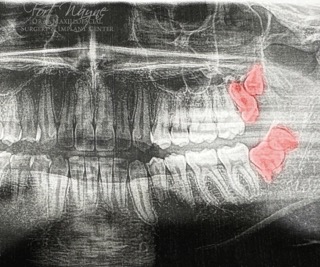

For many patients, wisdom tooth removal is an inevitable part of getting older. The “third molars” generally begin to erupt between the ages of 17 and 25. When they do not have adequate space to erupt, wisdom teeth may become impacted. This impaction can cause severe pain in the mouth and jaw, and many times extracting these teeth is the most common treatment option. Dr. Mulokozi Lugakingira is a highly specialized oral surgeon and performs wisdom teeth extractions on a regular basis. We strive to make your wisdom teeth extraction as painless as possible through gentle and less invasive modern procedures, under sedation. If you plan to see Dr. Lugakingira please watch the following video: